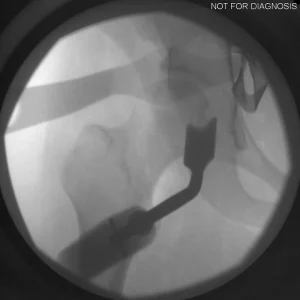

During a PAO, the surgeon carefully cuts the bone around the hip socket and repositions it to provide better coverage of the femoral head. The socket is then fixed in its new position using screws. The goal is to improve hip stability, reduce pain, and preserve the patient’s natural hip joint.

• Screws shown securing the acetabulum in its new position

• The socket is repositioned and fixed with screws

Screw Removal

In most cases, the screws are left in place. However, if they cause irritation, removal can be considered after the bone has healed, which is typically 9-12 months after the initial PAO.